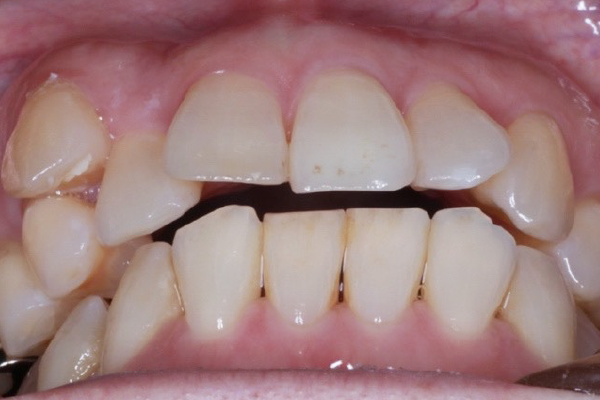

矯正治療後

Aさんは2年の治療を経て、歯並びが整いました。

笑顔が増えて、自信を持てるようになりました。

前歯で物を咬むことも出来るようになりました。もっと早くやれば良かったです!